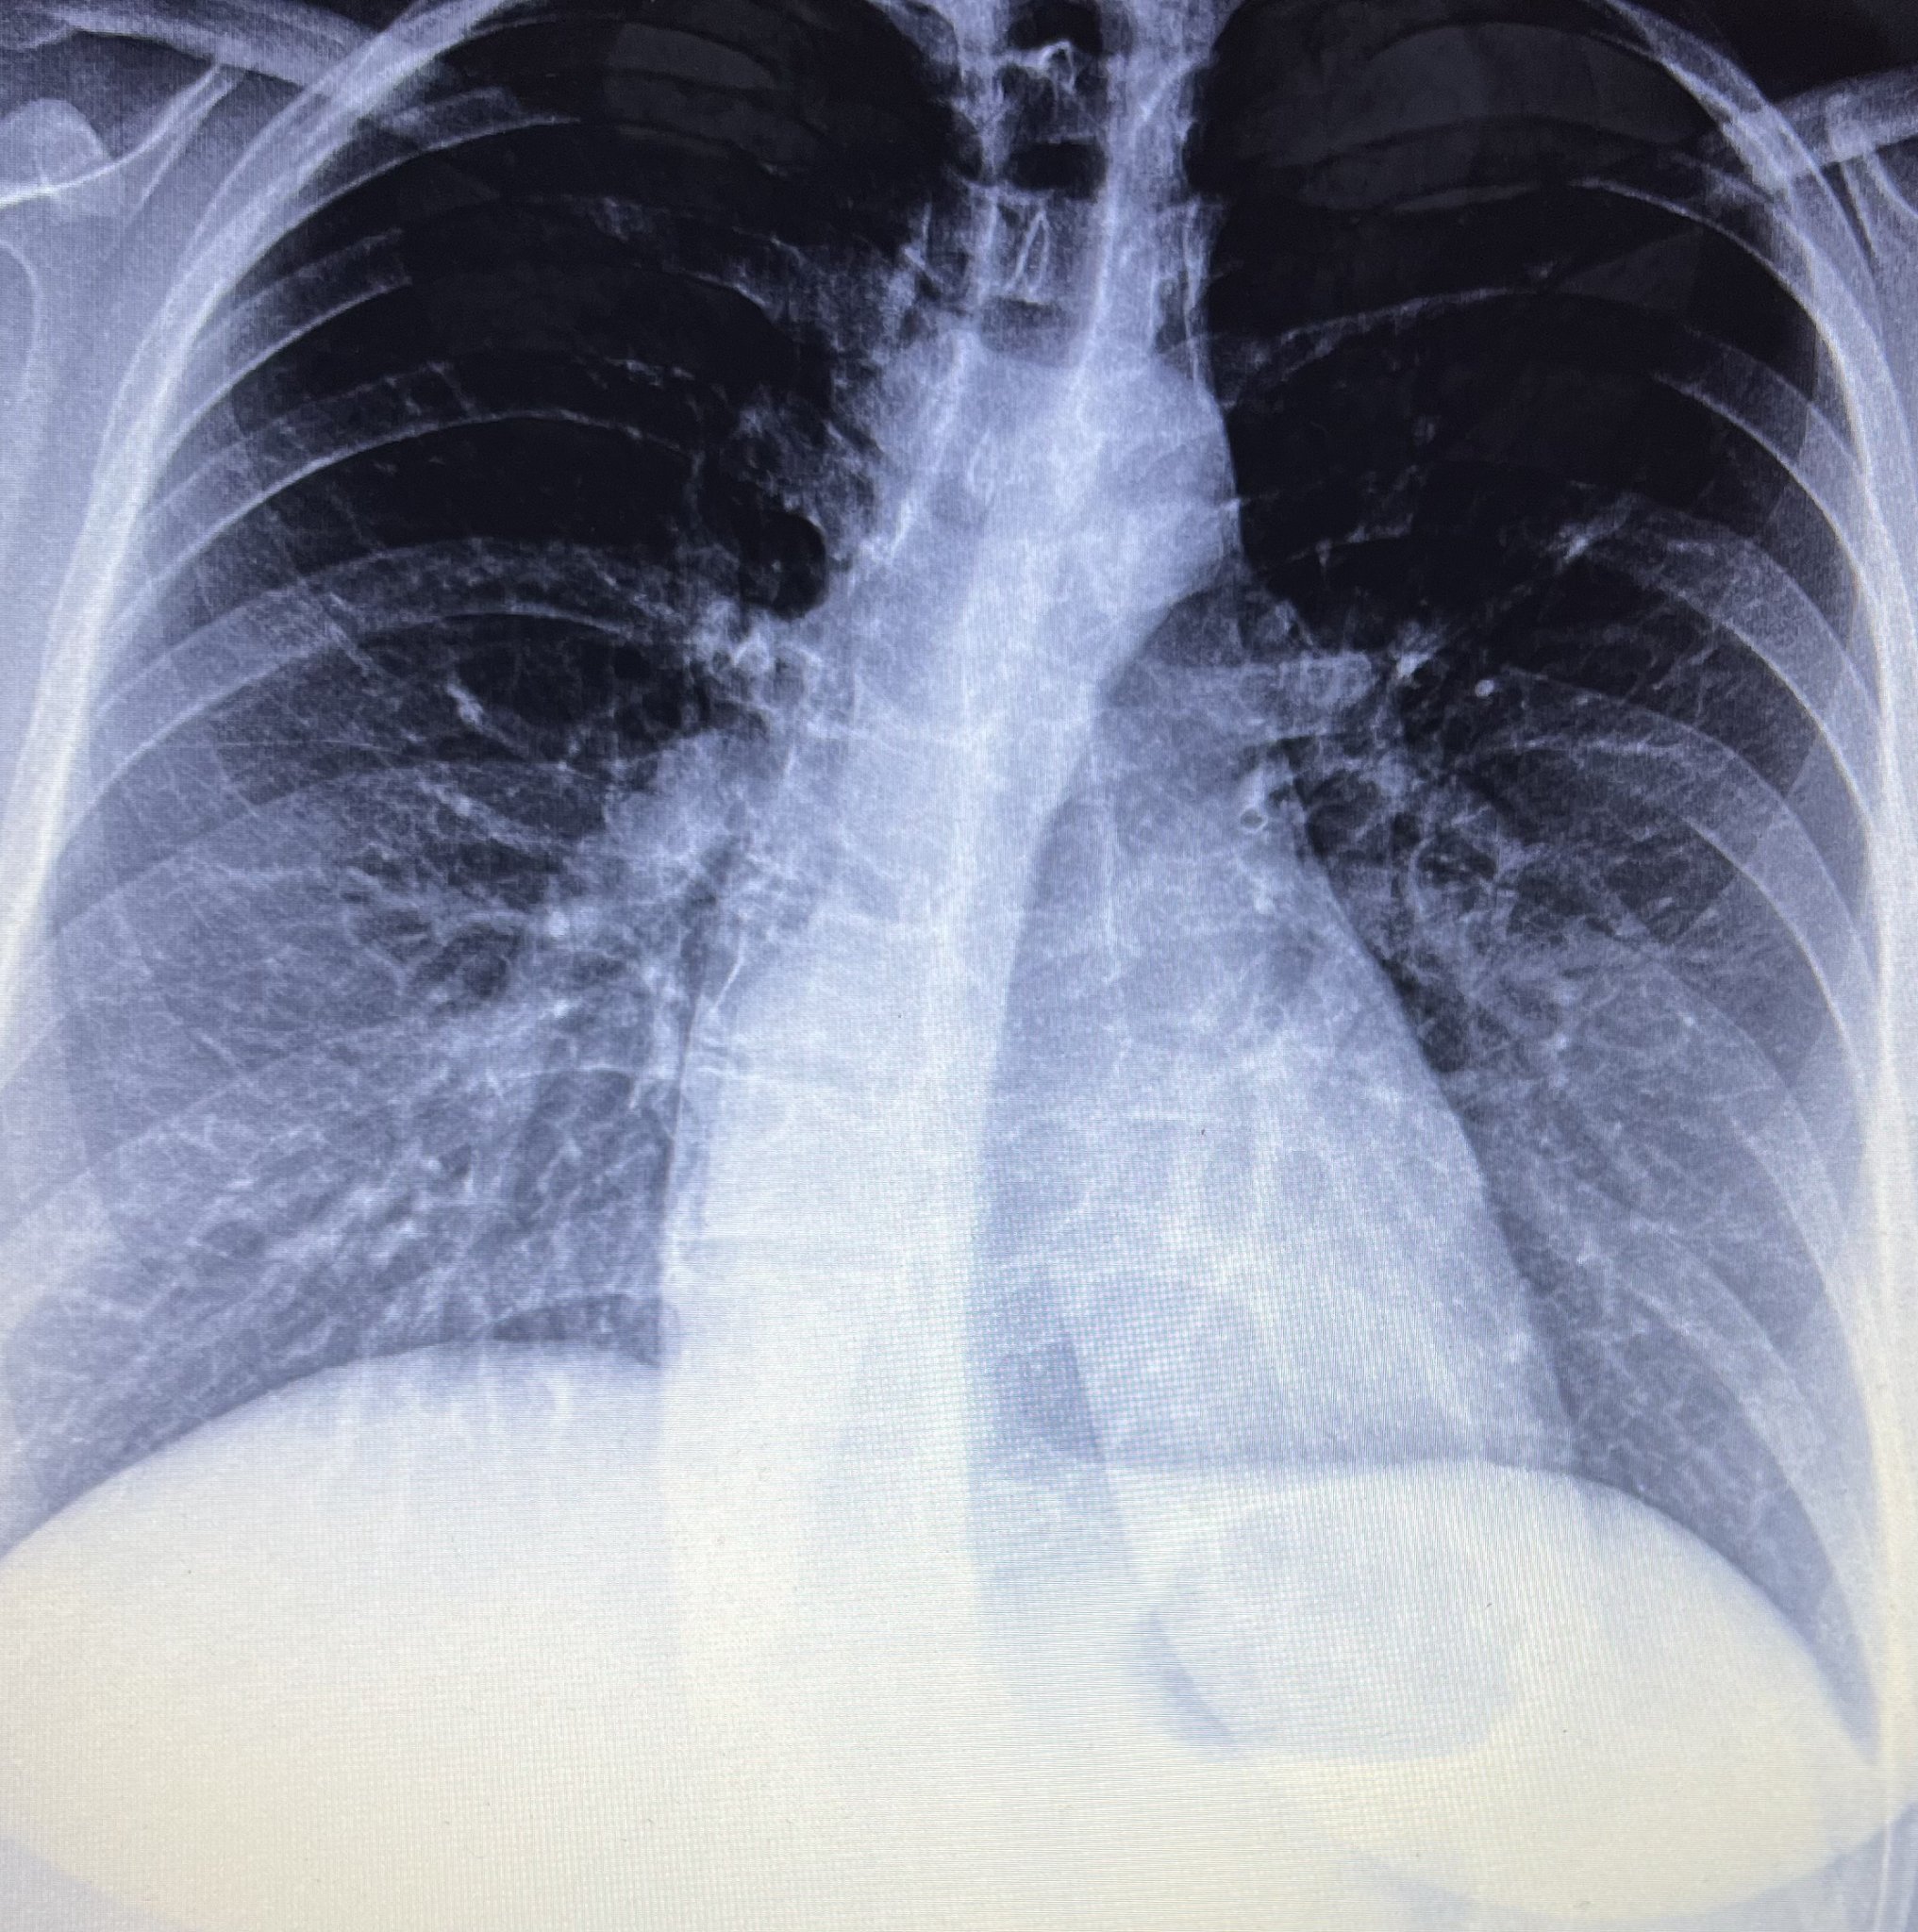

Здравейте, с кашлица съм от 3 месеца. Вчера си направих снимка на бял дроб , но тъй като лекарката е чак утре на работа много моля за някакви мнения , че ми е притеснено. Рентгенолога е написал усилен белодробен рисунък базално

.